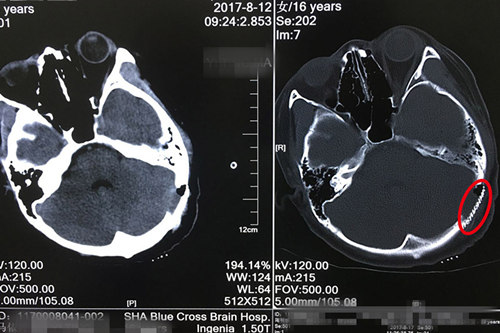

話雖然這么說,可是靜靜小腦內(nèi)的這個病灶已長成一顆花生那么大,將枕骨穿透了一個手指粗的洞。而且這個病灶與粗大的靜脈竇(靜脈匯合形成的血管腔,構(gòu)成特殊的顱內(nèi)靜脈管道,輸送顱內(nèi)靜脈血)緊密粘連,最狹窄的地方還不到1毫米的距離。既要把病灶切除干凈(防止復發(fā)),又不能損傷血管(如果血管破裂,后果不堪設想),手術室的助手醫(yī)生和護士都替侯主任捏一把汗。最后,憑借著多年積累下來的嫻熟技藝和沉穩(wěn)作風,侯主任完美切除了病灶,保留了血管,保護了腦組織,手術順利結(jié)束。

術后CT顯示:鈦網(wǎng)與顱骨結(jié)合緊密,未見明顯異常病灶。